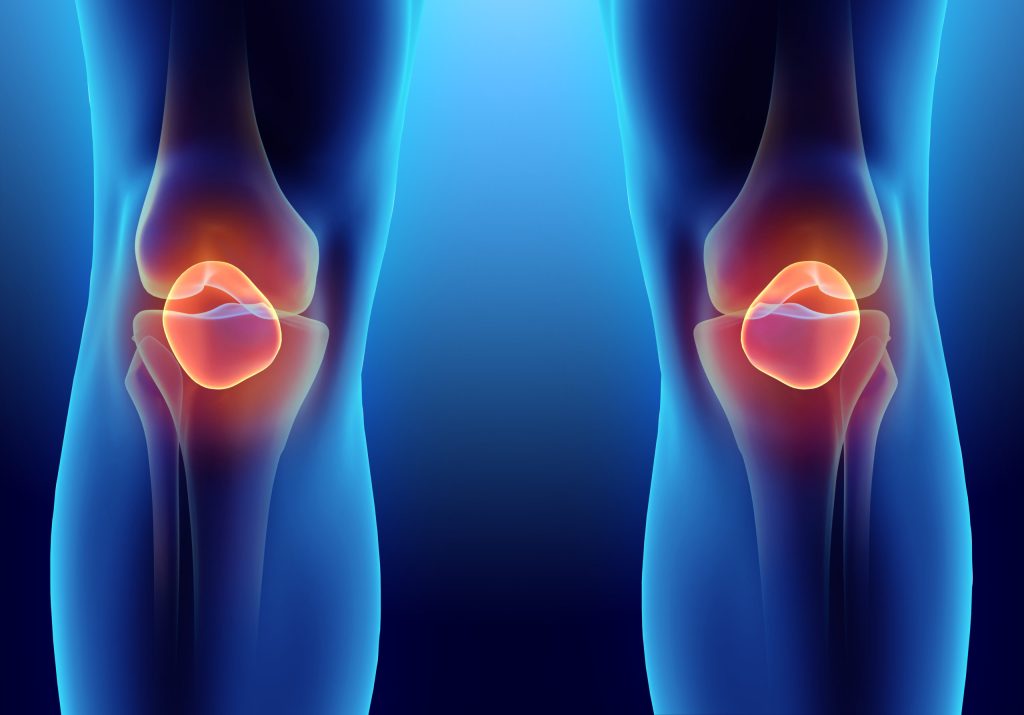

Tıptaki adıyla osteoartrit, diz eklemlerindeki kıkırdağın aşınması sonucu ortaya çıkan bir durumdur. Yaşlanma, genetik faktörler, yaralanmalar ve aşırı kullanıma bağlı olarak gelişebilir. Diz kireçlenmesi, günlük yaşamı olumsuz etkileyen bir rahatsızlıktır ve doğru tedavi yöntemleri ile yönetilebilir.

Diz çevresinde görülen hastalıklar arasında artrit, menisküs yaralanmaları, tendonit ve bursit bulunmaktadır. Artrit, eklemin iltihaplanması sonucu ağrı ve hareket kısıtlılığına neden olurken; menisküs yaralanmaları, dizdeki kıkırdak yapının hasar görmesiyle oluşur. Tendonit, tendonların iltihaplanmasıdır ve bursit, diz çevresindeki bursaların iltihaplanmasını ifade eder. Bu hastalıklar, genellikle spor yaralanmaları, aşırı kullanım veya yaşlanma nedeniyle ortaya çıkar. Erken teşhis ve tedavi önemlidir.

Dizde, özellikle hareket ederken ya da uzun süre oturduktan sonra ağrı hissedilir. Ağrı genellikle günün ilerleyen saatlerinde daha belirgin hale gelir. Diz eklemi, iltihaplanma sonucu şişebilir. Bu durum, eklemdeki sıvı birikimi nedeniyle oluşur. Özellikle sabahları veya uzun süre hareketsiz kaldıktan sonra dizi hareket ettirmekte zorluk çekilebilir. Diz hareket ettirildiğinde gıcırtı veya çatırdama sesi duyulabilir. Bu, kıkırdağın aşınması sonucu oluşan bir durumdur. Dizin tam olarak bükülmesi veya açılması zorlaşabilir, bu da günlük aktiviteleri etkileyecek derecede bir kısıtlama yaratır.

Yaş ilerledikçe kıkırdak yapısında doğal bir bozulma meydana gelir. 50 yaş üstü bireylerde diz kireçlenmesi riski artar. Spor aktiviteleri veya fiziksel işlerde sürekli diz eklemlerini zorlamak, kıkırdağın aşınmasına yol açabilir. Aşırı kilolu bireylerde diz eklemi, vücut ağırlığını taşıdığı için daha fazla baskı altında kalır. Ailede öyküsü olan bireylerin bu duruma yakalanma riski yüksektir. Geçmişte dizde meydana gelen yaralanmalar veya ameliyatlar, diz kireçlenmesi gelişimine zemin hazırlayabilir.